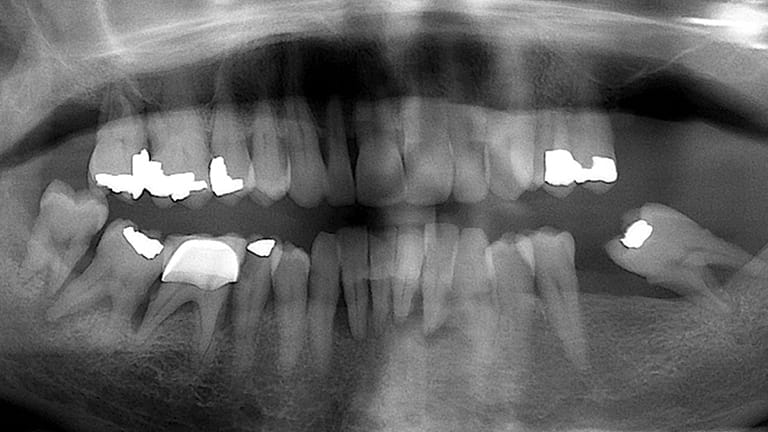

Bad Tooth

Below is a few examples of what DENTAL IMPLANTS can do for you and your smile!